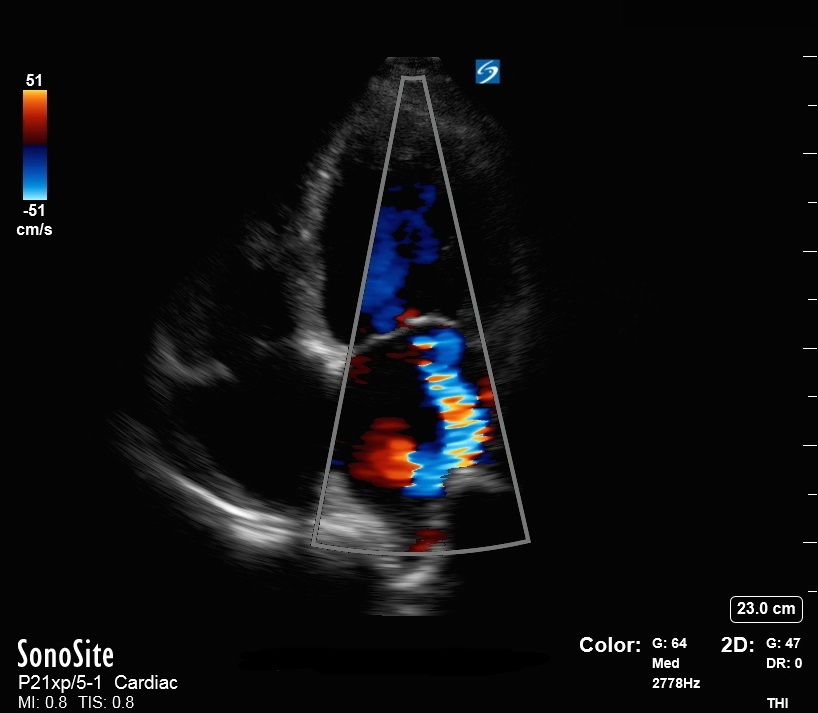

僧帽弁逆流カラー画像の頂端4室表示